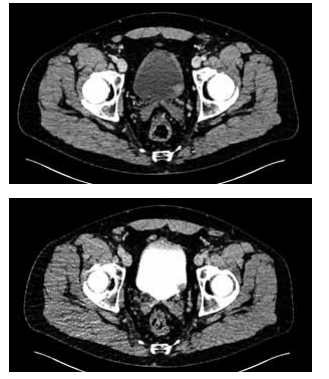

Observe a imagem da tomografia a seguir:

(Arquivo pessoal; imagem usada com autorização)

Qual diagnóstico deve ser considerado com base nos achados da tomografia e qual diagnóstico concomitante está associado à sua hipótese?